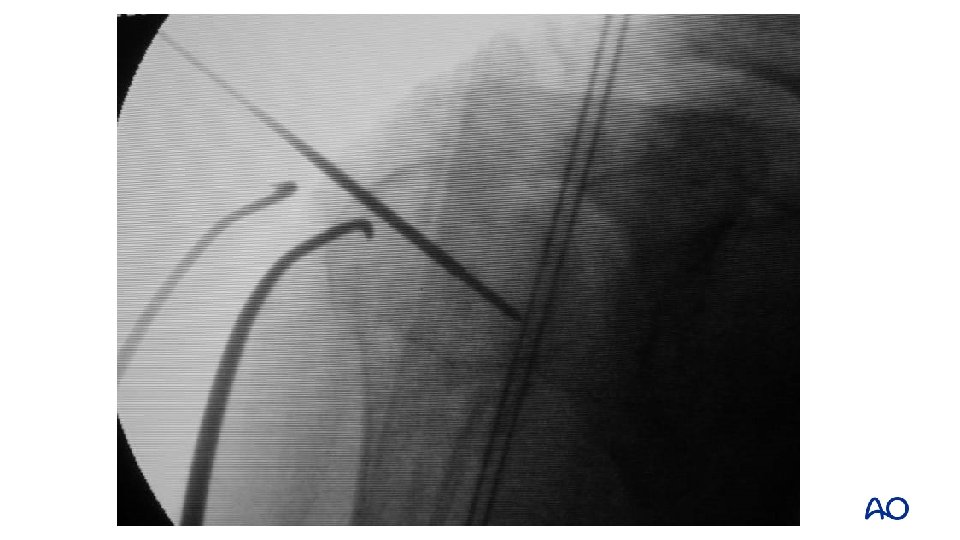

Proximal humerus—intramedullary nailing Correct entry portal is essential for the final reduction result

Proximal humerus—intramedullary nailing Prior to fixation: • Reduction and identification of the entry point Techniques: • Manipulation of the arm • Reduction tools (eg, K-wires)